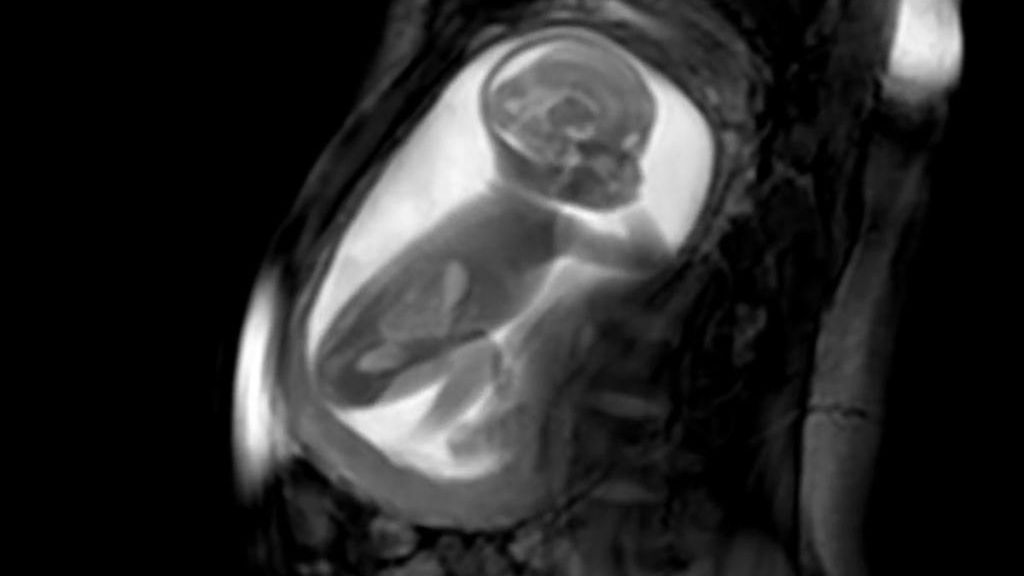

Przełom. Po raz pierwszy zobaczyli tak dokładnie serce nienarodzonego dziecka

Naukowcy stworzyli bezprecedensową technologię, dzięki której można przyjrzeć się sercu dziecka, gdy jest ono jeszcze w łonie matki.

Wszystko dzięki specjalnie zaprojektowanym modelom 3D. Ciężarne kobiety zostały przeskanowane w maszynie MRI, a następnie komputery o niezwykle dużej mocy stworzyły trójwymiarowe modele bijących serc nienarodzonych dzieci - podaje bbc.com.

Technologia pomoże w walce z wadami serca. Zespół lekarzy zrzeszonych w fundacji King's College London and Guy's and St Thomas's twierdzi, że nowa technika badań poprawi opiekę nad dziećmi z wrodzoną wadą serca. Dzięki niej możliwe będzie szybkie wykrycie oraz wdrożenie planu leczenia

Naukowcy twierdzą, że ich technologia może być bardzo łatwo zastosowana w codziennych szpitalnych zabiegach.